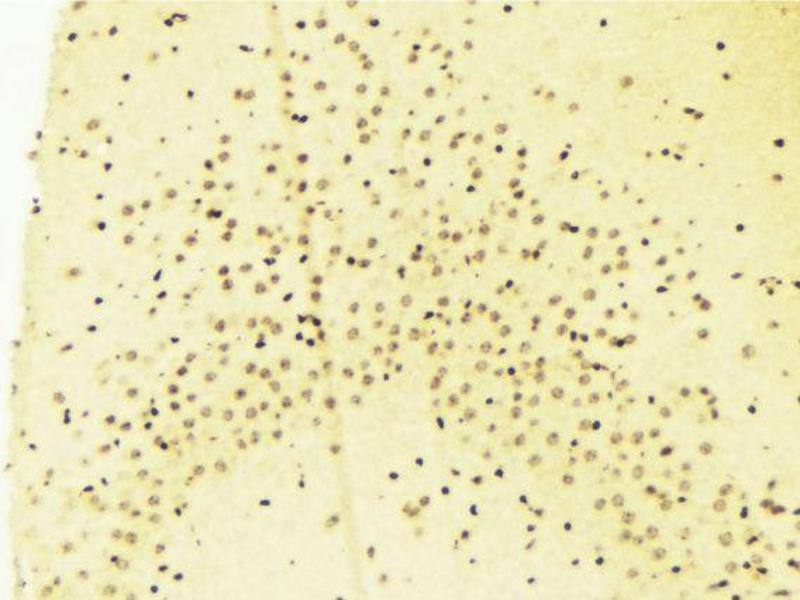

HDAC7 Reactivité: Humain WB, ELISA, IHC Hôte: Lapin Polyclonal unconjugated

HDAC7 Reactivité: Humain, Souris WB, ELISA, IHC Hôte: Lapin Polyclonal unconjugated